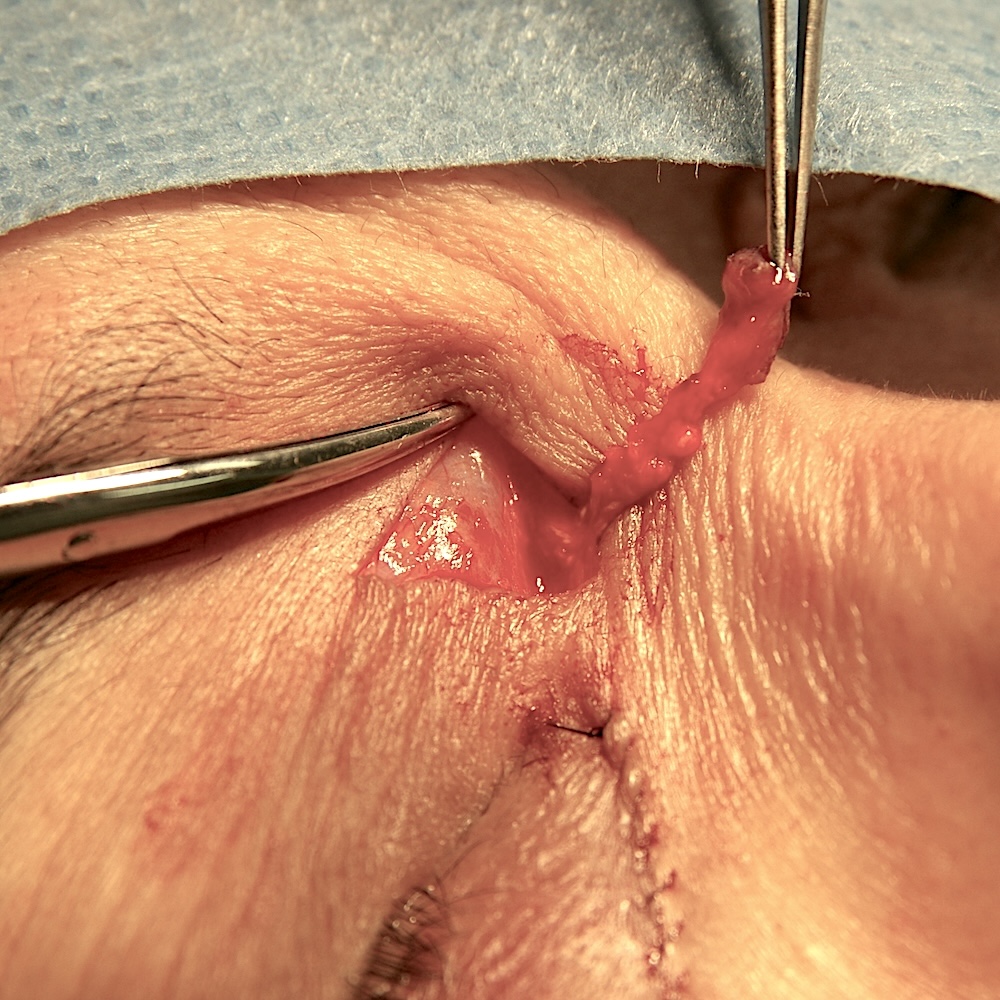

左の写真は、眼瞼手術のページでも紹介した再発症例(他院形成外科で切除したがとりきれておらず、切開線に沿って再発した)の術中写真です。やはり眼輪筋に染み込むように黄色い腫瘍が深くまで侵入しているのがわかります。